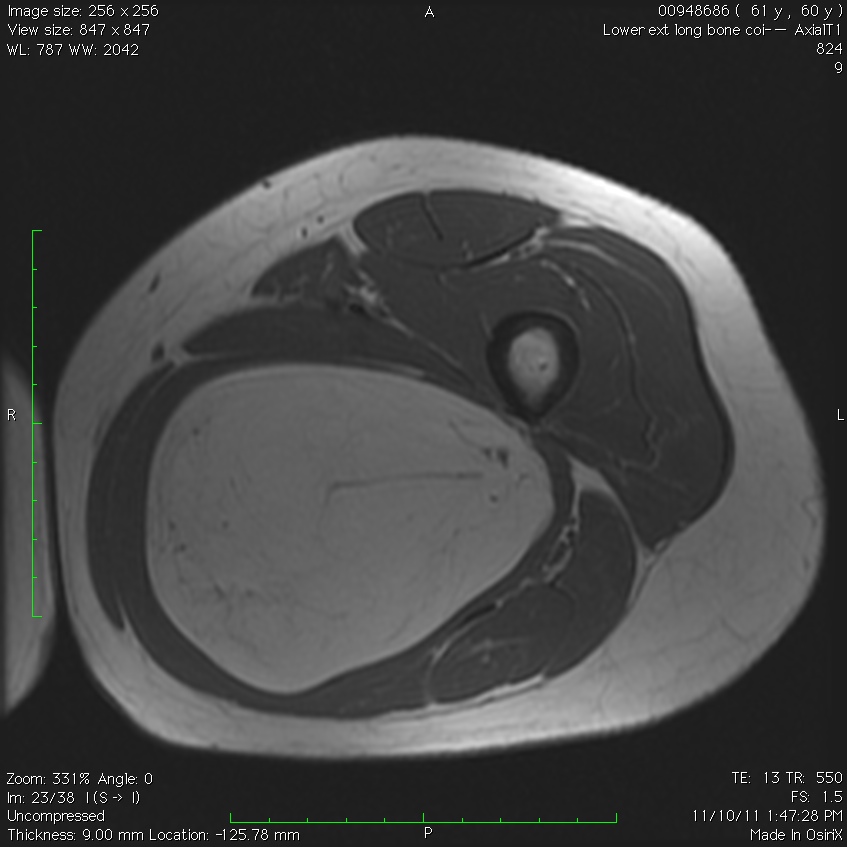

MRI

• Follows the signal characteristics of subcutaneous fat on all sequences

• T1: High Signal

• T2: Intermediate Signal; Low Signal with Fat Suppression

• Minimal or No enhancement with gadolinium

Fig. 1A, 1B, 1C, 2A, 2B, 2C: MRI of a lipoma: T1- weighted images shows an homogeneous mass in the posterior compartment of the thigh with high signal, saturates on fat saturated sequences with no or minimal enhancement. On T2-weighted images demonstrate an intermediate signal on FSE T2, saturates (becomes dark) on fat saturated sequences.